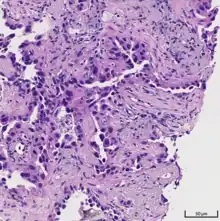

Acinar pattern.[16]

• acinar predominant [19]